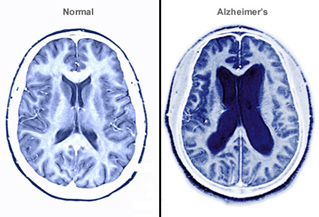

阿兹海默症会导致神经细胞坏死,大脑的各部分组织损失。随着病情加重,大脑实质组织会逐步萎缩,脑室(大脑内部的腔隙,内含脑脊液)则逐步增大。阿兹海默症造成的破坏会阻碍脑细胞之间的交流,对记忆力、语言能力和理解能力产生损害。